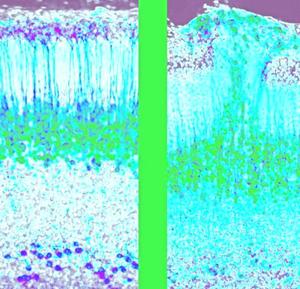

Descubren en ratones un nuevo circuito cerebral embrionario